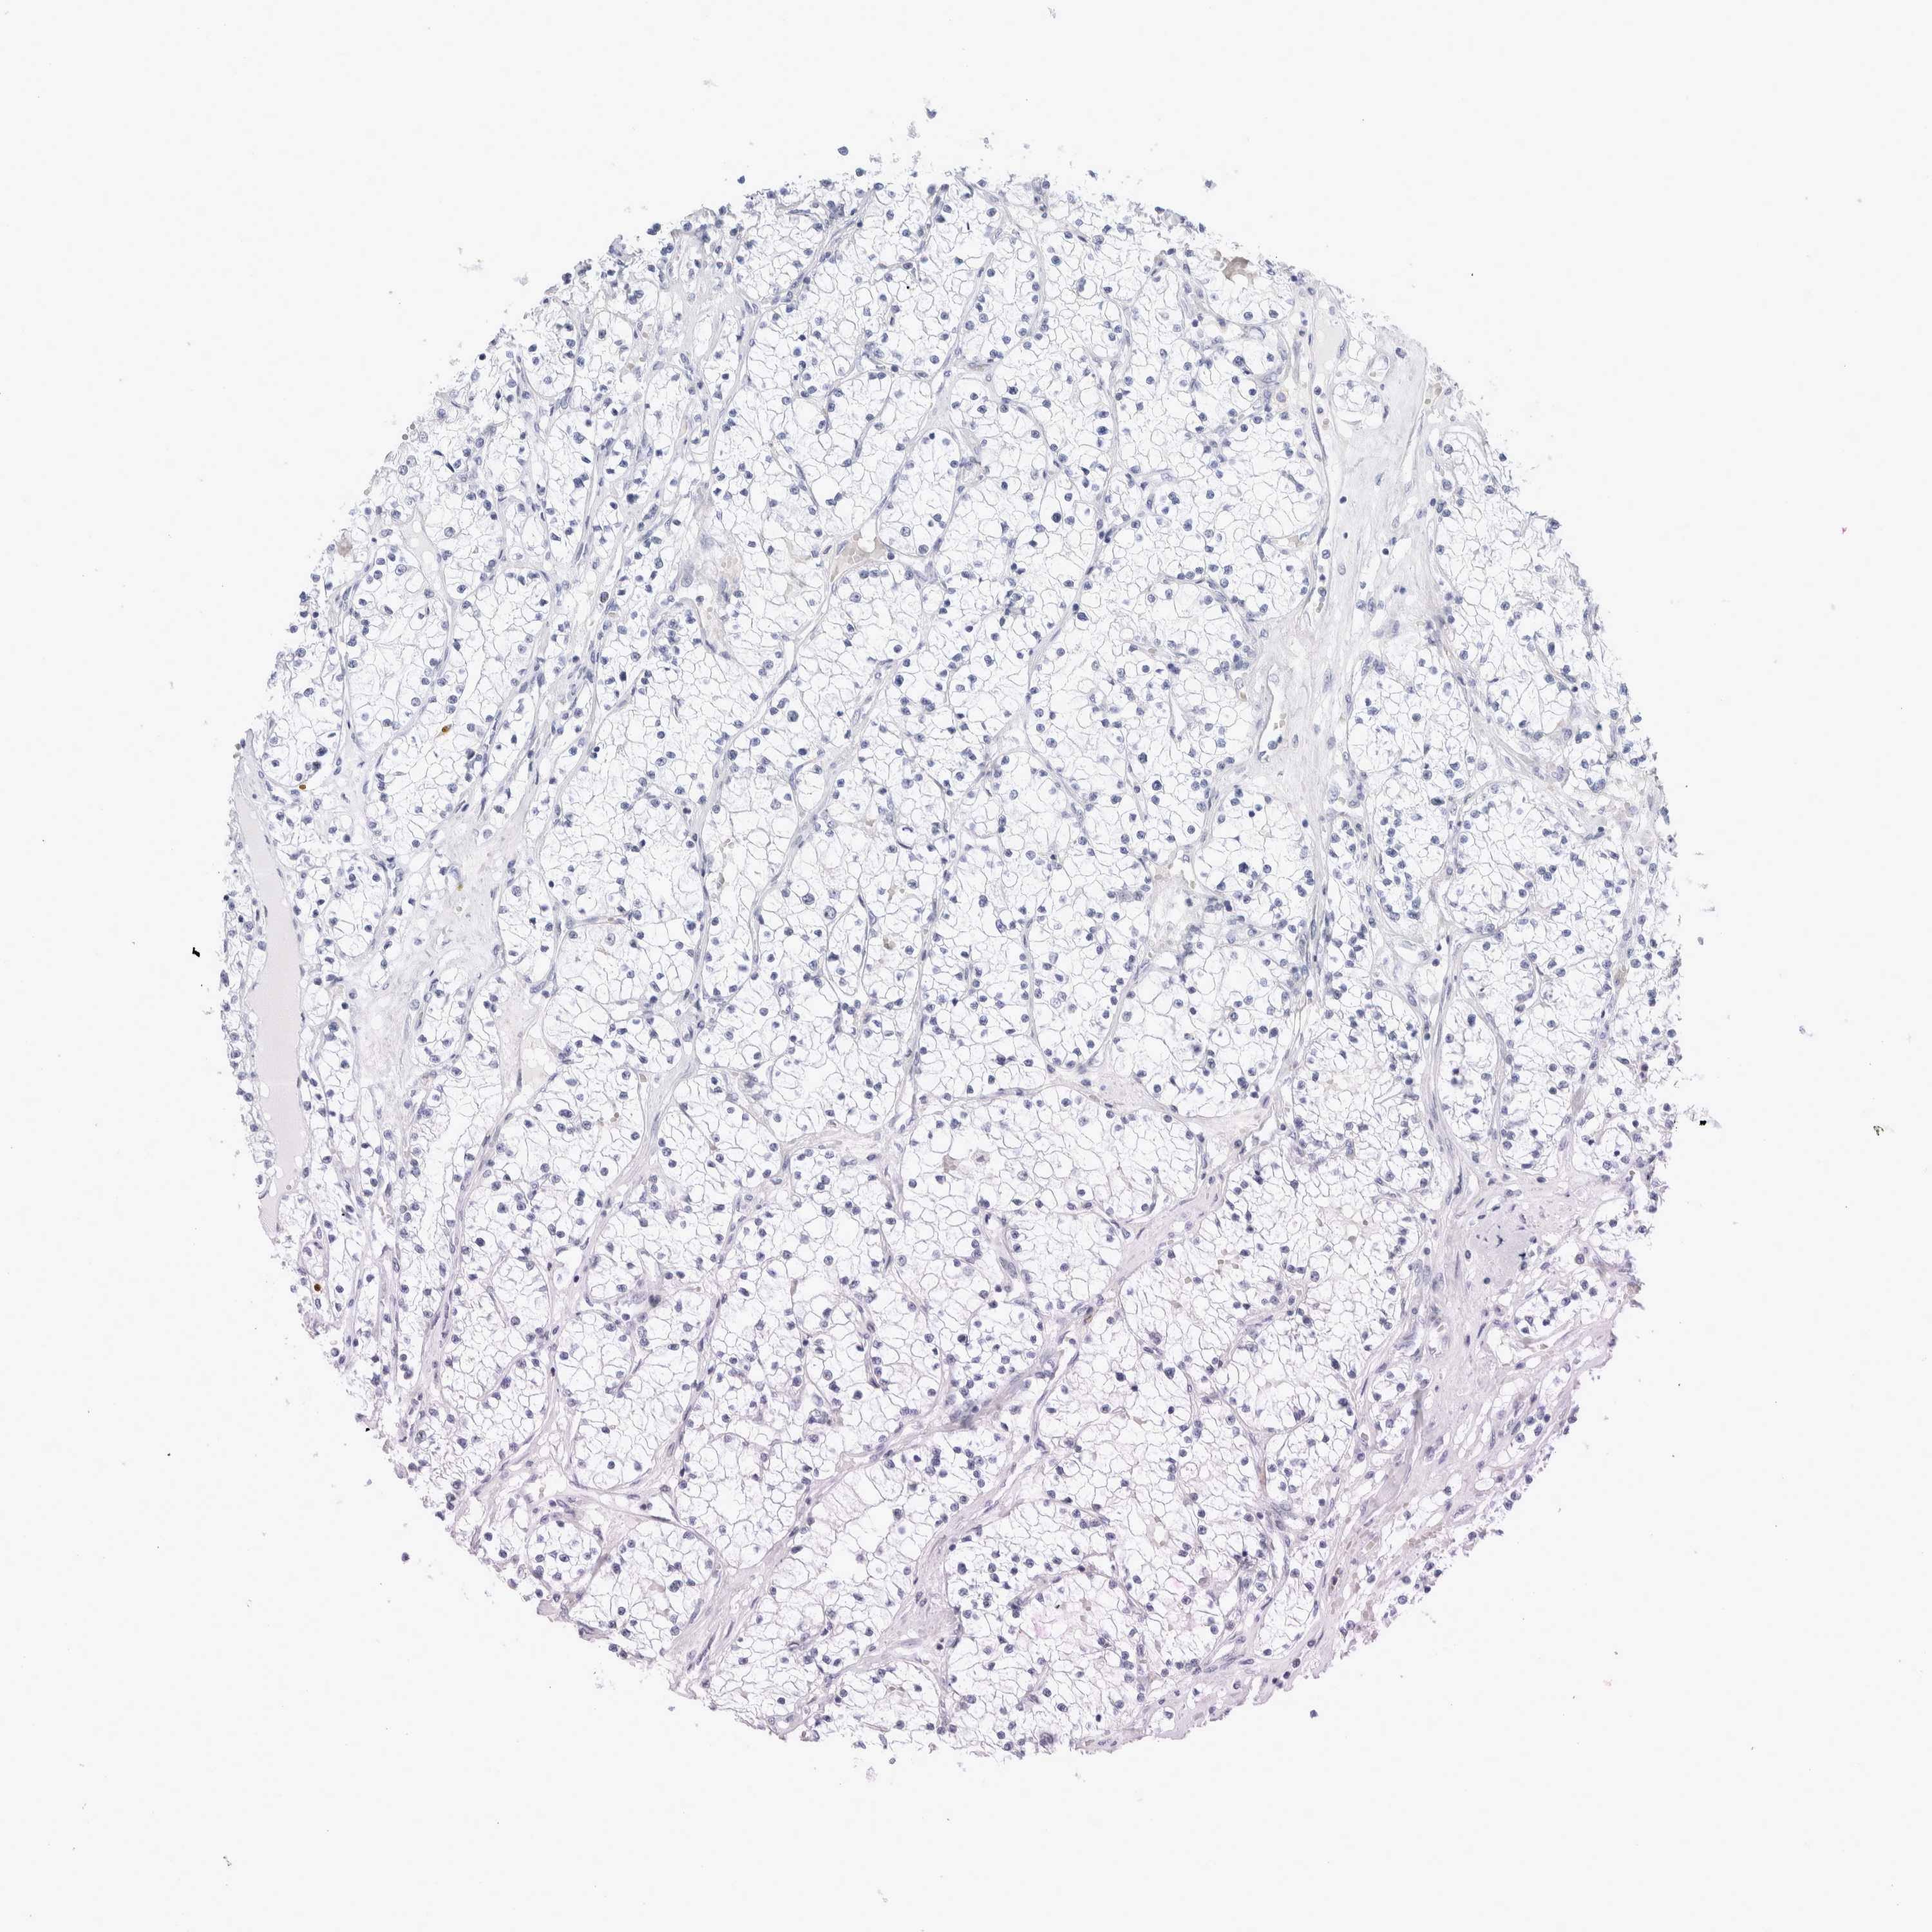

KIDNEY RENAL PAPILLARY CELL CARCINOMA (TCGA) - Interactive survival scatter ploti

The Survival Scatter plot shows the clinical status (i.e. dead or alive) for all individuals in the patient cohort, based on the same data that underlies the corresponding Kaplan-Meier plots. Patients that are alive at last time for follow-up are shown in blue and patients who have died during the study are shown in red.

The x-axis shows the expression levels (FPKM) of the investigated gene in the tumor tissue at the time of diagnosis. The y-axis shows the follow-up time after diagnosis (years). Both axes are complimented with kernel density curves demonstrating the data density over the axes. The top density plot shows the expression levels (FPKM) distribution among dead (red) and alive patients (blue). The right density plot shows the data density of the survived years of dead patients with high and low expression levels respectively, stratified using the cutoff indicated by the vertical dashed line through the Survival Scatter plot. This cutoff is automatically defined based on the FPKM cutoff that minimizes the p-score. The cutoff can be changed by dragging the vertical line or by entering a cutoff value in the square labeled "Current cut-off".

Under the Survival Scatter plot the p-score landscape (black curve; left axis) is shown together with dead median separation (red curve; right axis). Dead median separation is the difference in median mRNA expression between patients who have died with high and low expression, respectively. It is calculated as follows: median FPKM expression of dead patients with high expression - median FPKM expression of dead patients with low expression. This is intended to aid the user in visually exploring custom cutoffs and the associated p-scores and dead median separation.

Individual patient data is displayed and can be filtered by clicking on one or more of the category buttons on the top of the page. Categories describing expression level and patient information include: high, low, alive, dead, female, male and tumor stages. The scale of the x-axis can be toggled between linear and log-scale by clicking on the "x log" button. Mouse-over function shows TCGA ID, patient information and mRNA expression (FPKM) for each patient.

& Survival analysisi

Kaplan-Meier plots summarize results from analysis of correlation between mRNA expression level and patient survival. Patients were divided based on level of expression into one of the two groups "low" (under cut off) or "high" (over cut off). X-axis shows time for survival (years) and y-axis shows the probability of survival, where 1.0 corresponds to 100 percent.

Survival analysis data not available.

TCGA RNA samplesi

RNA-seq data is reported as average FPKM (number Fragments Per Kilobase of exon per Million reads), generated by the The Cancer Genome Atlas (TCGA) .

Normal distribution across the dataset is visualized with box plots, shown as median and 25th and 75th percentiles. Points are displayed as outliers if they are above or below 1.5 times the interquartile range. FPKM values of the individual samples are presented next to the box plot.

Average pTPM 0.2

Number of samples 282